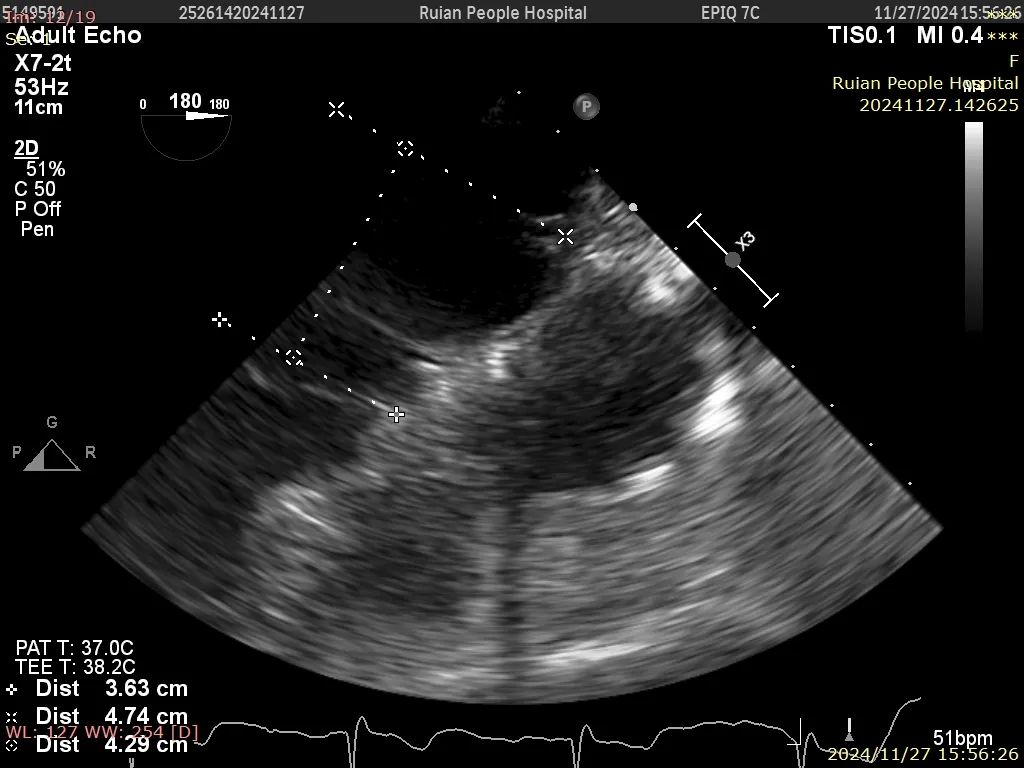

房间隔穿刺:实际穿刺高度4.29cm

术中房间隔穿刺 双房切面

术中房间隔穿刺 主动脉短轴

术中房间隔穿刺高度4.29cm